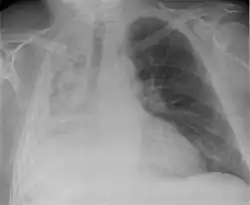

Atelectasis of a person's right lung

Atelectasis of the right lower lobe seen on chest X-ray.

Clinically significant atelectasis is generally visible on chest X-ray; findings can include lung opacification and/or loss of lung volume. Post-surgical atelectasis will be bibasal in pattern. Chest CT or bronchoscopy may be necessary if the cause of atelectasis is not clinically apparent. Direct signs of atelectasis include displacement of interlobar fissures and mobile structures within the thorax, overinflation of the unaffected ipsilateral lobe or contralateral lung, and opacification of the collapsed lobe. In addition to clinically significant findings on chest X-rays, patients may present with indirect signs and symptoms such as elevation of the diaphragm, shifting of the trachea, heart and mediastinum; displacement of the hilus and shifting granulomas.[13]